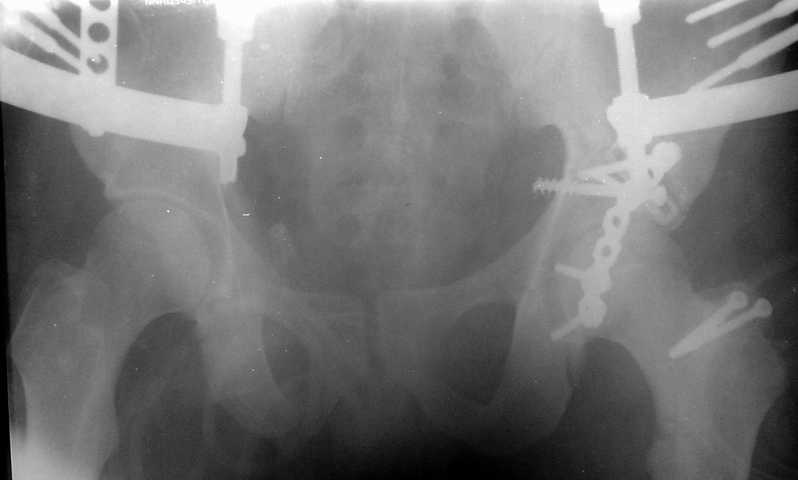

Тяжелая политравма у юноши С. 20 лет - 23.02.20030г. - падение с высоты 8 этажа. В настоящее время состояние стабилизировалось, возможен остеосинтез. Аппарат наложен при поступлении. Д-З: Политравма Перелом С2 б/смещения Перелом левого бедра(см.снимок),правой голени (стабилизирован),обеих пяточных костей со смещением,таза (см.снимок) Нужно ли произвести синтез таза? или ограничиться синтезом бедра? каким??

Оговорюсь сразу, что DHS или DCS не имею, состояние больного позволяет произвести и синтез таза, но надо ли это, учитывая множественность переломов др.локализации? Извиняюсь, что нет др. снимков и за качество, сканер с незким разрешением. Благодарю за советы !

Пока видно, что имеется тяжелый оскольчатый перелом вертлужной впадины, который надо открыто синтезировать. Для уточнения диагноза необходимо сделать косые проекции (Judet views). Не помешала бы КТ.

Для уточнения диагноза необходим обзорный снимок таза и Judet проекции. Судя по присланной короткой рентгенограмме, один из компонентов перелома - отрыв свода, точно имеется ступенеобразная деформация нагружаемой поверхности и без открытой репозиции ничего хорошего не будет. Если в ближайшую неделю восстановительная опеперация не будет сделана, то лучше потом и не пытаться, а ждать сращения бедра для эндопротеза.

Травма 17 ноября 2002 г., поступил к нам 1 декабря, оперирован 8-го - открытая репозиция, остеосинтез пластинками и винтами. Учитывая повреждение переднего полукольца справа, и крестца и крестцово-подвздошного сочленения слева, наложили аппарат на 2 месяца.

Для экономии места привожу интра- и послеоперационный обзорный снимок, без дополнительных проекций.